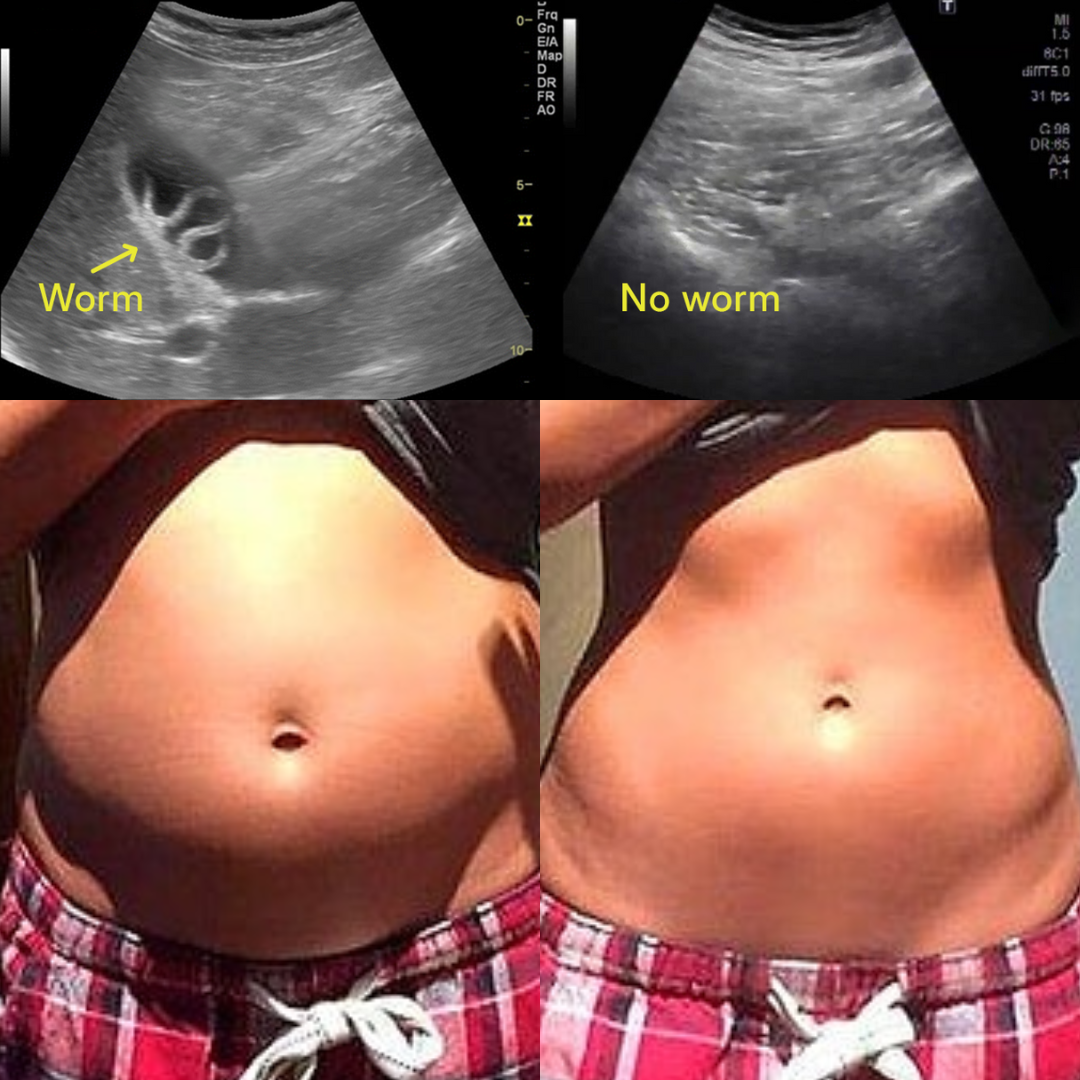

Hidden toxins, parasites, and microplastics are draining your energy and aging you faster than you realize.

Every breath, sip, and bite exposes you to a toxic storm of parasites, metals, plastics, and hidden chemicals. They build up in your body, draining your energy, clouding your mind, and accelerating aging from the inside. This isn't your fault — your body was never built to fight off this many invaders alone.

Eliminate parasites to reduce bloating and unexplained cravings. Bind and flush heavy metals to support liver and brain health. Capture microplastics to help you feel lighter and more energized.